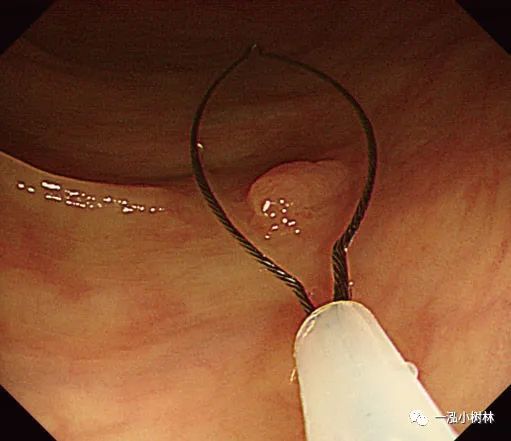

图5d 对病变进行机械性横切

图5e 对病变进行机械性横切

图5f 息肉取出后出血

图5g 黏膜出血止血

图5h 可见息肉边缘正常黏膜的标本